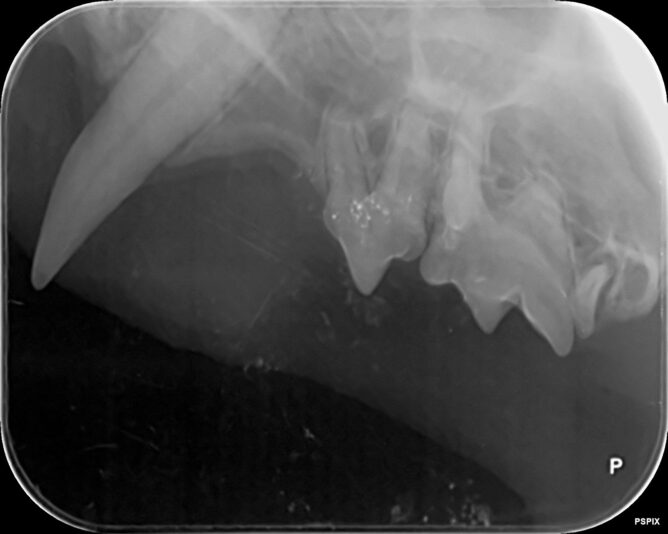

case gegeneraliseerde ontsteking peridontale ruimte

We hebben deze dentale RXen genomen van een jonge oosterse korthaar met chronische gingivitis sinds de geboorte. Op deze Rxen zie ik een verbreed paradontium en een te witte ‘lijn’ bij de aflijning van het alveolair bot. Is er een aandoening die beschreven is bij onze katten en past bij dit beeld? Hoe gaan we verder te werk? Meloxicam lijkt…